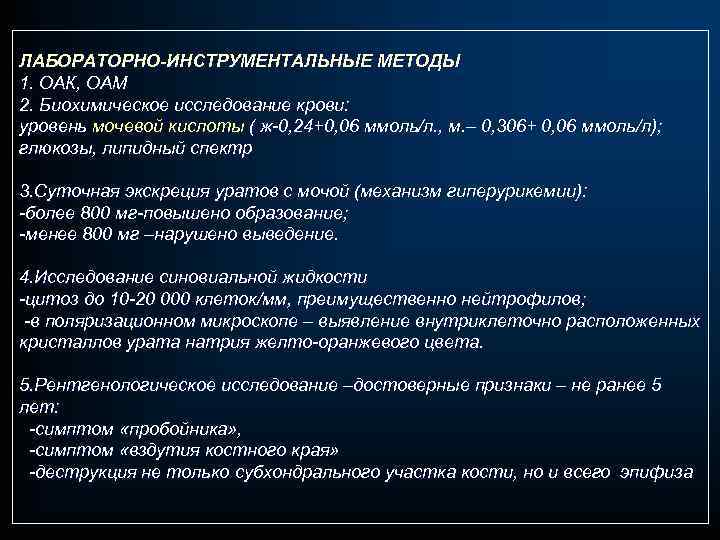

ЛАБОРАТОРНО-ИНСТРУМЕНТАЛЬНЫЕ МЕТОДЫ 1. ОАК, ОАМ 2. Биохимическое исследование крови: уровень мочевой кислоты ( ж-0, 24+0, 06 ммоль/л. , м. – 0, 306+ 0, 06 ммоль/л); глюкозы, липидный спектр 3. Суточная экскреция уратов с мочой (механизм гиперурикемии): -более 800 мг-повышено образование; -менее 800 мг –нарушено выведение. 4. Исследование синовиальной жидкости -цитоз до 10 -20 000 клеток/мм, преимущественно нейтрофилов; -в поляризационном микроскопе – выявление внутриклеточно расположенных кристаллов урата натрия желто-оранжевого цвета. 5. Рентгенологическое исследование –достоверные признаки – не ранее 5 лет: -симптом «пробойника» , -симптом «вздутия костного края» -деструкция не только субхондрального участка кости, но и всего эпифиза

ЛАБОРАТОРНО-ИНСТРУМЕНТАЛЬНЫЕ МЕТОДЫ 1. ОАК, ОАМ 2. Биохимическое исследование крови: уровень мочевой кислоты ( ж-0, 24+0, 06 ммоль/л. , м. – 0, 306+ 0, 06 ммоль/л); глюкозы, липидный спектр 3. Суточная экскреция уратов с мочой (механизм гиперурикемии): -более 800 мг-повышено образование; -менее 800 мг –нарушено выведение. 4. Исследование синовиальной жидкости -цитоз до 10 -20 000 клеток/мм, преимущественно нейтрофилов; -в поляризационном микроскопе – выявление внутриклеточно расположенных кристаллов урата натрия желто-оранжевого цвета. 5. Рентгенологическое исследование –достоверные признаки – не ранее 5 лет: -симптом «пробойника» , -симптом «вздутия костного края» -деструкция не только субхондрального участка кости, но и всего эпифиза